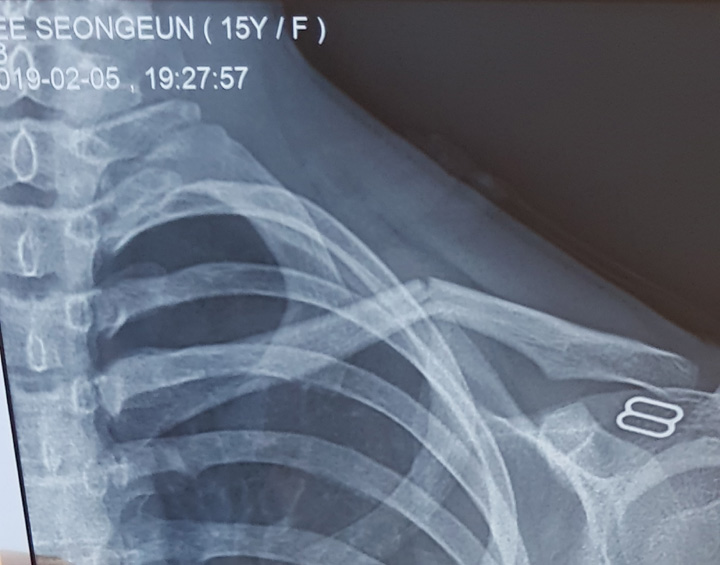

이번 기도편지는 저희 가정의 막내 성은이의 쇄골 골절 소식부터 전해야 할 것 같습니다. 지난 2월 초 겨울 농구 시즌을 맞아 인근 학교인 AIS 체육관에서의 농구 경기 중 드리블하던 성은이의 좌측 쇄골을 상대방 선수가 팔꿈치로 강하게 내리쳤습니다. 순간 성은이는 무척 큰 통증을 느꼈지만 시합 중인지라 몇 분 가량 더 참고 뛰다가 벤치로 들어왔고 쇄골 부위의 이상을 의심한 간호 선생님이 왼팔을 붕대로 고정해 준 그대로 집에 돌아왔습니다. 현관문을 여는 성은이의 얼굴에는 옅은 미소가 흘렀지만 상당한 통증에다 팔을 움직이기 힘들어하기에 무슨 일이 발생했음을 직감하고 급히 X-선 촬영을 위해 나섰습니다. 그리고 역시나.... 좌측 쇄골 골절을 확인했지요.

때가 이미 늦은 시간인지라 응급진료를 하는 클리닉에서 정형외과 진료를 받았는데 골절로 인해 깁스가 필요하다는 소견이었고 스카치 붕대같은 가벼운 깁스 재료를 구하기 힘든 밤 중인지라 어쩔 수 없이 왼팔을 굽힌 채 석고붕대로 좌측 상반신을 고정할 수밖에 없었습니다. 아이들이 운동하다보면 다칠 수도 있지만 가장 차분하고 조심성 많은 막내 성은이가 오빠, 언니도 겪지 않은 쇄골 골절을 입었다는 사실이 믿기지 않았습니다. 통증을 이겨내며 괜찮다며 상반신 깁스를 하고 침대에 눕는 모습이 참 마음 아팠습니다.

다음 날 밤, 석고붕대의 석고가 흘러내려 관절 부위를 누르는 탓에 골반이나 팔꿈치 쪽 불편함이 심해져 다시 그 병원을 찾았습니다. 전날과 다른 정형외과 선생님이 당직이었는데 깁스를 제거하고 쇄골 부위만 고정하는 8장 붕대 같은 보조기를 알마티에서 찾아보자고 제안하셨습니다. 처음 듣는 얘기였습니다.(나중에 알고보니 한국에서는 일반적으로 그렇게 한다는군요) 이후 우여곡절 끝에 쇄골 골절에 사용되는 고정 장치를 정형외과 보조기 매장에서 어렵게 구해 깁스를 대체할 수 있었습니다.

1주 가량 상반신 깁스를 하는 동안에는 무겁기도 하고 식사도 제대로 못하는 등 어려움이 많았지만 사진 속의 고정기를 착용한 뒤로는 불편함이 많이 줄어습니다. 하지만 골절부위의 통증은 생각보다 꽤 오래갔고 2번 X선 촬영을 거치며 뼈가 잘 붙고 있는지 기도하며 지켜봐야 했습니다. 감사하게도 6주 정도 쇄골 고정장치를 하고 난 뒤로 골절 부위도 잘 붙고 조금씩 왼팔을 이전처럼 머리 위로 올릴 수 있게 되었습니다. 덕분에 겨울 내내 성은이는 많이 힘들었습니다.

3. 막내 성은이의 쇄골 골절은 이제 많이 좋아졌지만 오랫동안 왼 팔을 제대로 사용하지 않았기에 운동재활이 필요합니다. 관련 분위가 완전하게 치유, 회복되도록 기도해 주세요. 아울러 첫째 형민이는 오는 6월 6일 이곳 텐샨학교를 졸업합니다. 2011년 8월, 알마티 텐샨학교 5학년으로 들어왔는데 이제 12학년을 마치고 졸업하게 됩니다. 한국으로 대학 진로를 결정하고 준비 중인데 주님 안에서 늘 마음의 평안과 기쁨을 유지하도록 기도해 주세요. 둘째 시은이는 오는 5월 10일부터 18일까지 텐샨학교 단기팀의 일원으로 인도의 한 고아원을 방문해서 현지 아이들에게 간증과 성경공부, 찬양과 활동을 통해 예수님을 증거하게 됩니다. 지난 몇 달 동안 기도하며 준비했는데 이번 기도편지에 꼭 기도제목으로 올려달라고 부탁했습니다. 인도에서 만날 고아원 아이들과 시은이의 마음이 새로운 변화를 경험하도록 기도해 주세요.